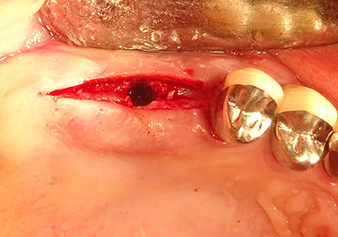

The Schneiderian membrane is stretched 1.5-2 mm above the bony access

Fig.4: Intermediate check: The bone height above the maxillary sinus floor is approx. 4 mm palatal and buccal; the Schneiderian membrane is stretched 1.5-2 mm above the bony access.